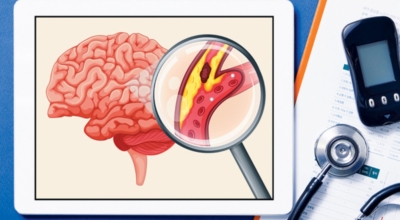

뇌졸중 종류

뇌졸중은 뇌경색과 뇌출혈 두가지로 나뉘게 돼요. 먼저 뇌경색은 뇌혈관이 막혀 영양분과 산소를 주는 피가 통하지 않는 상태로 원은은 크게 세 가지로 나눌 수 있는데요 동맥경화증이 생겨 좁아진 부위로 인하여 혈액공급이 부족해지거나 좁아지다가 결국 막혀버리는 경우, 큰 혈관에서 분지한 작은 혈관들이 고혈압 등으로 압박을 받으면 혈관이 막히는 경우가 있습니다.

또한 심장 판막질환이나 심방세동 또는 심근병 등등의 심장 질환이 있는 경우 심장에서 혈전이 만들어지고 그게 뇌로 흘러가게 되면 뇌혈관을 막게 되는 경우가 있답니다. 뇌출혈은 뇌경색과 반대로 뇌혈관이 터져서 생기는 뇌내 출혈과 거미막하 출혈로 나누게 돼요. 거미막하출혈은 혈관벽의 약한 부분이 부풀어 오르는 뇌동맥류가 터지는 경우와 관련성이 크다고 해요.